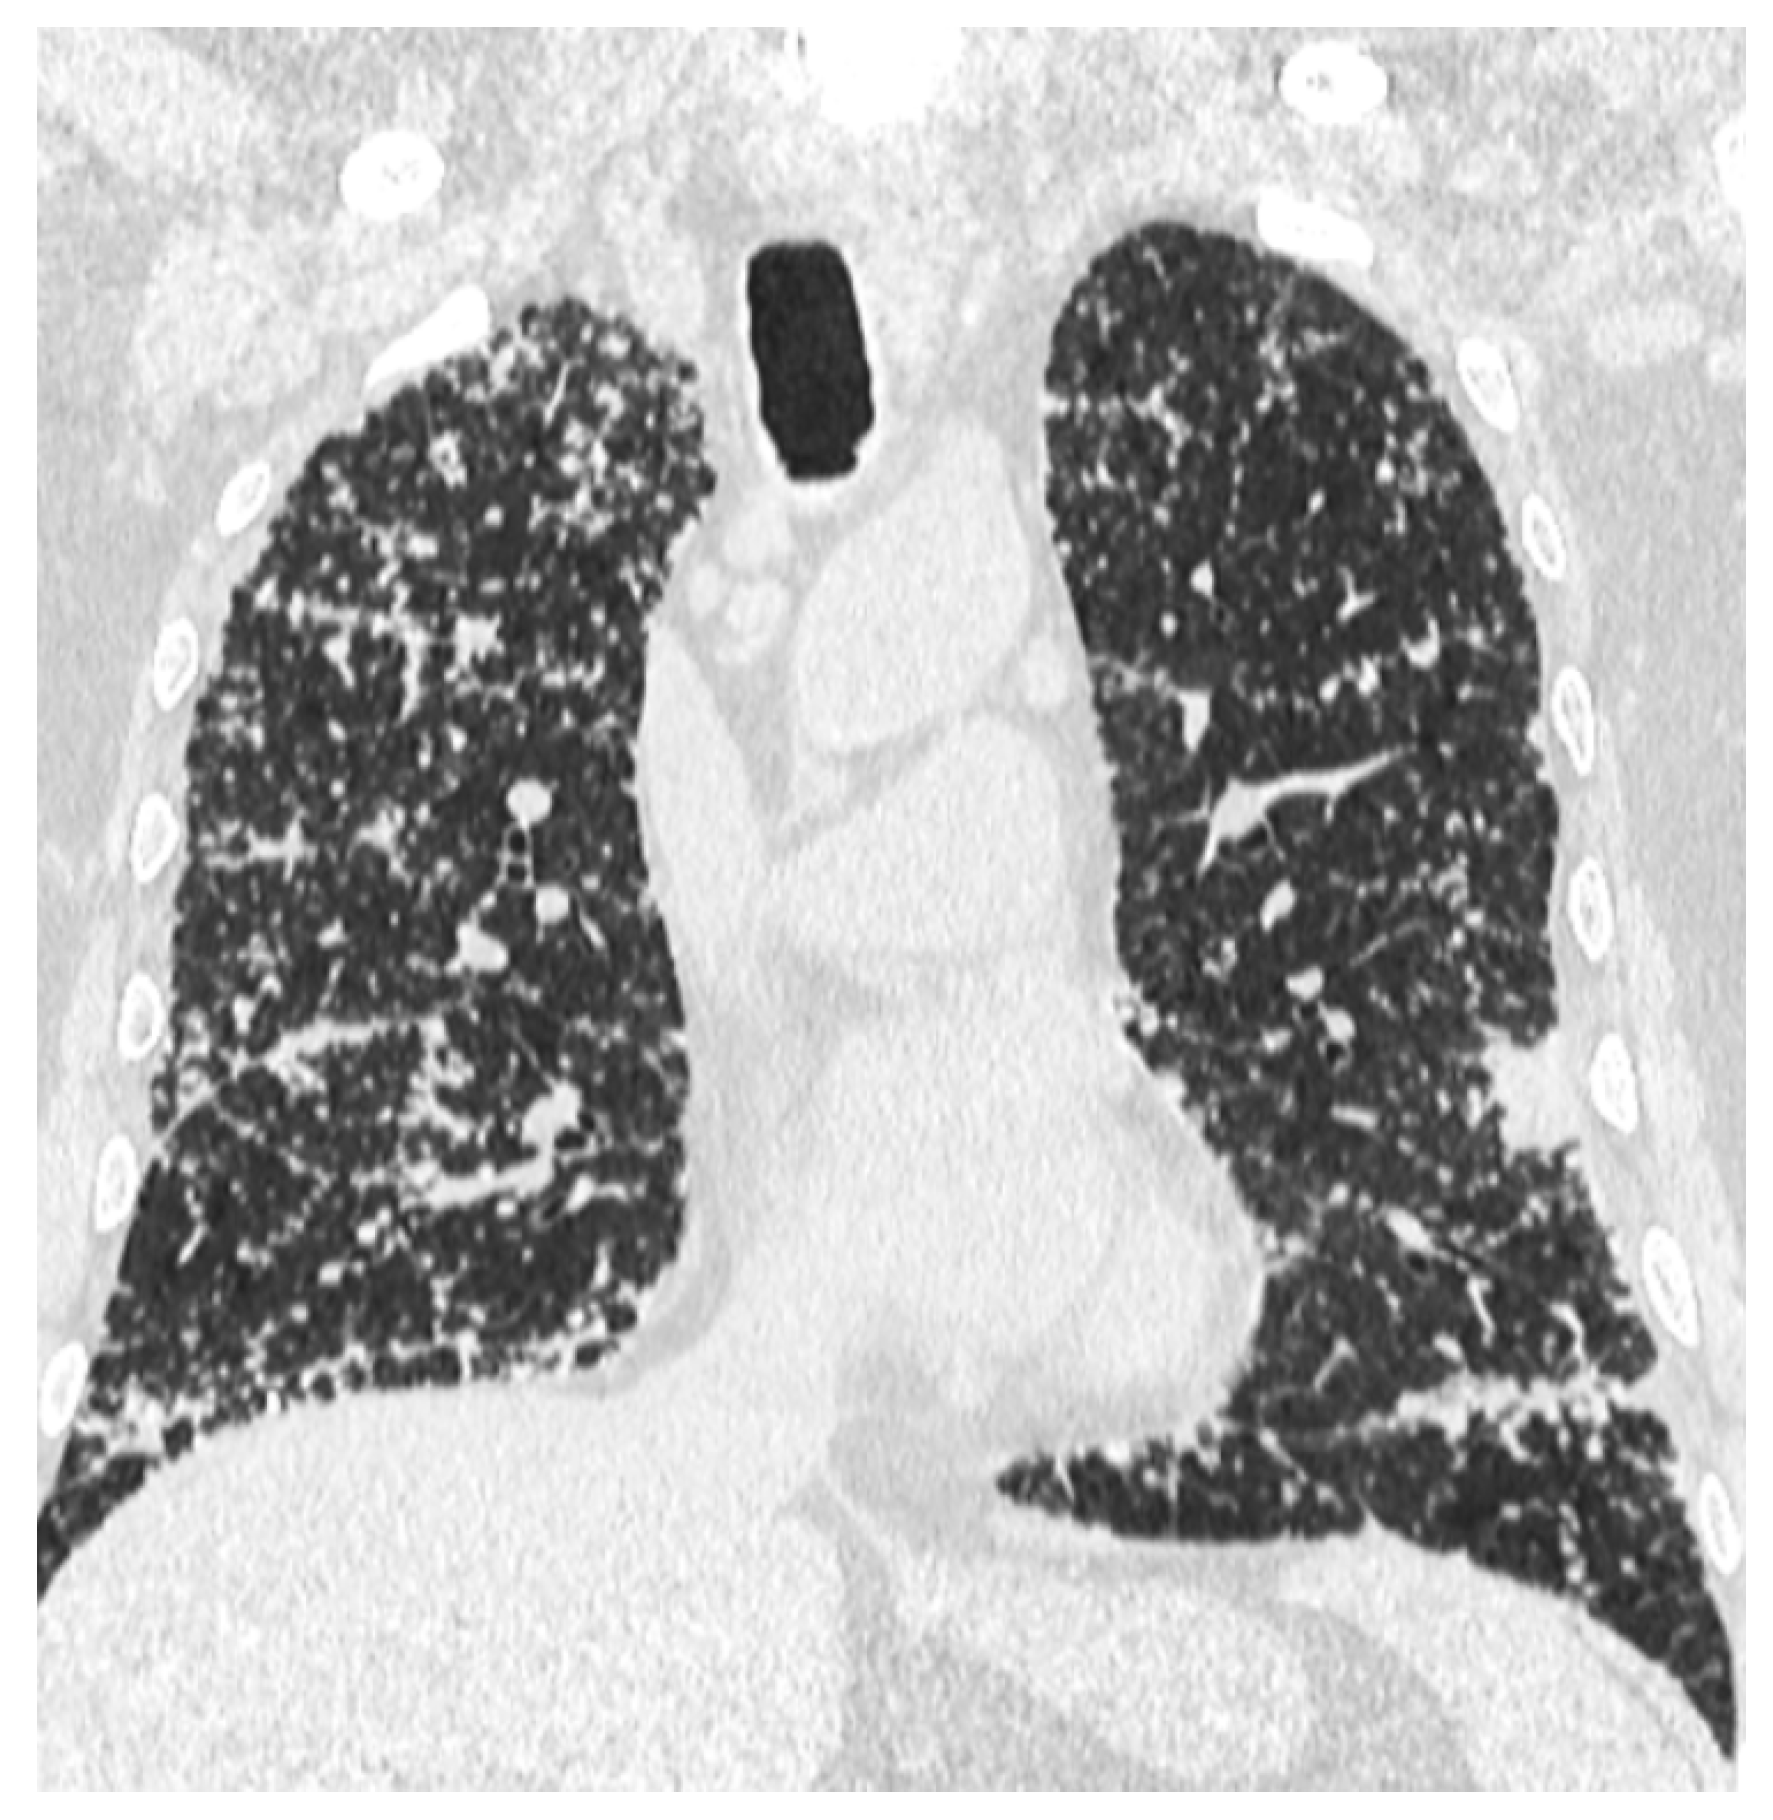

2. Case Report